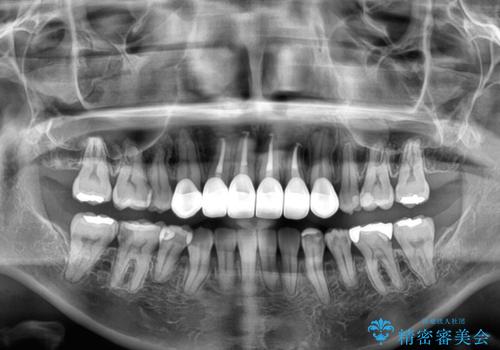

上顎前歯4本は、以前むし歯により神経をすべて取り除かれており、その影響で既に変色を起こしている状態でした。

4本とも歯根部先端の骨が炎症により吸収していることがレントゲン写真から示唆されたため、矯正治療後に4本を再根管治療し、その後上顎6歯をオールセラミッククラウンにて補綴治療することとしました。

歯並びだけでなく、歯の色も明るくなり、すっきりとした口元の印象となりました。